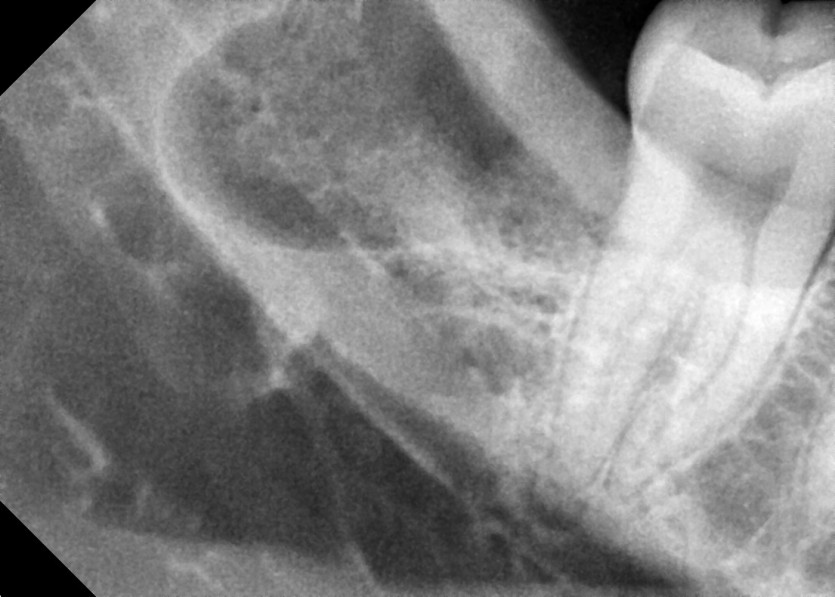

#18,48 사랑니 발치

구강 외과 전문의가 당일 발치했습니다.